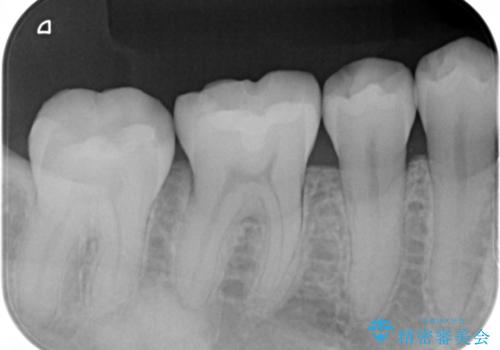

- 矯正治療が終了して歯並びが綺麗になると、元々入っていた銀歯が気になってきたとのことで適合の良いセラミックへのやり替えを行いました。

適合不良の補綴物は二次的な虫歯発生のリスクが高まります。

自費診療で用いられる材料は保険適応の材料に比べて、より精密で適合の良い被せ物作ることができるため、長期的な虫歯のリスクを大幅に減らすことが可能です。